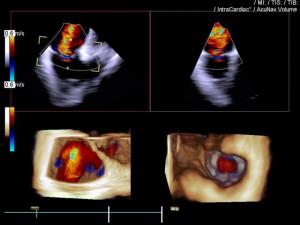

Siemens Healthineers has announced that it has received CE Mark for the AcuNav Volume ICE (intracardiac echocardiography) catheter, an imaging guide that provides real-time, wide-angle visualisation of heart anatomy during structural heart and electrophysiology procedures.